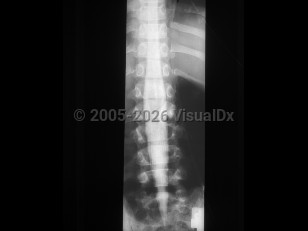

Low back pain, Neuropathy peripheral, 50-59 year old Female

Axial low back pain

Lumbar radiculopathy

Osteoporotic vertebral compression fracture

Spondylolysis

Ankylosing spondylitis

Spondylolisthesis

Lumbar spinal stenosis